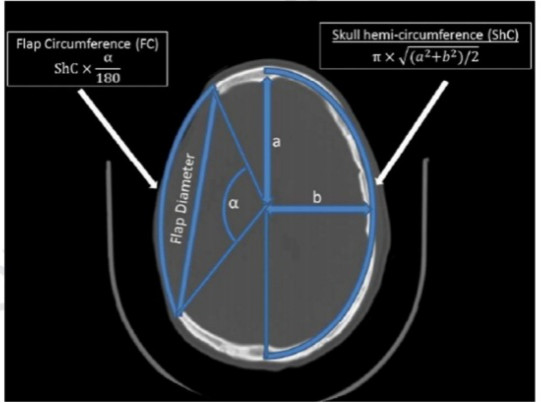

在术后CT上,测量头颅前后最大(AP)径。使用近似椭圆周长方程:2π√(a²+b²)/2)/2,计算头颅半周长;其中a等于AP径的1/2,b等于横径的1/2。使用椭圆圆弧方程√(∆x²+∆y²)计算骨窗皮瓣椭圆弧长度。然后根据图1中的公式计算骨窗皮瓣和颅骨半周的大小及比率。结合皮瓣周长与颅骨半周的比率和临床变量,使用Microsoft Excel统计分析均值、范围、中位数、连续变量的Student t检验、分类变量的Pearson’s 2检验以及散点图误差线的置信度99%CI。

图1. 计算头颅骨窗皮瓣与对侧头颅半周大小。